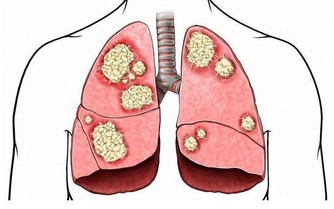

研究顯示,全球每年新發胃癌有40%以上發生在中國,而且85%以上的胃癌患者被確診時已經到了中晚期,其五年生存率迅速將到20%以下。

人們常說“人食五穀雜糧,孰能無疾”,而飲食入口,首先影響的就是胃。而且胃癌,大多是“拖”出來的!因為胃癌早期具有隱蔽性,它之所以難發現,是因為它跟普通胃病症狀很相似,而胃病又太過普遍,所以即使出現也被一拖再拖,最終到了晚期。

這3類人是胃癌“高危”人群!

3、慢性胃病人群

患有胃癌癌前病變的人群,如:慢性萎縮性胃炎、慢性胃潰瘍、腸息肉和切除了部分胃的人群,一級家族成員中有胃癌患者的人,要特別警惕胃癌的靠近。